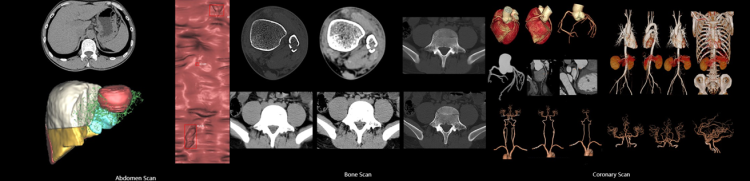

Anke ANATOM P428, optimum iş akışını sağlayabilmek ve yüksek kaliteli görüntüler verebilmek için özel teknolojilerle donatılmış 128 kesit bir bilgisayarlı tomografi sistemidir.

Yeni nesil OptiWave dedektörü sayesinde ALARA prensibine uygun şekilde kayıpsız ve fazlasıyla net görüntüleme performansı sunar.